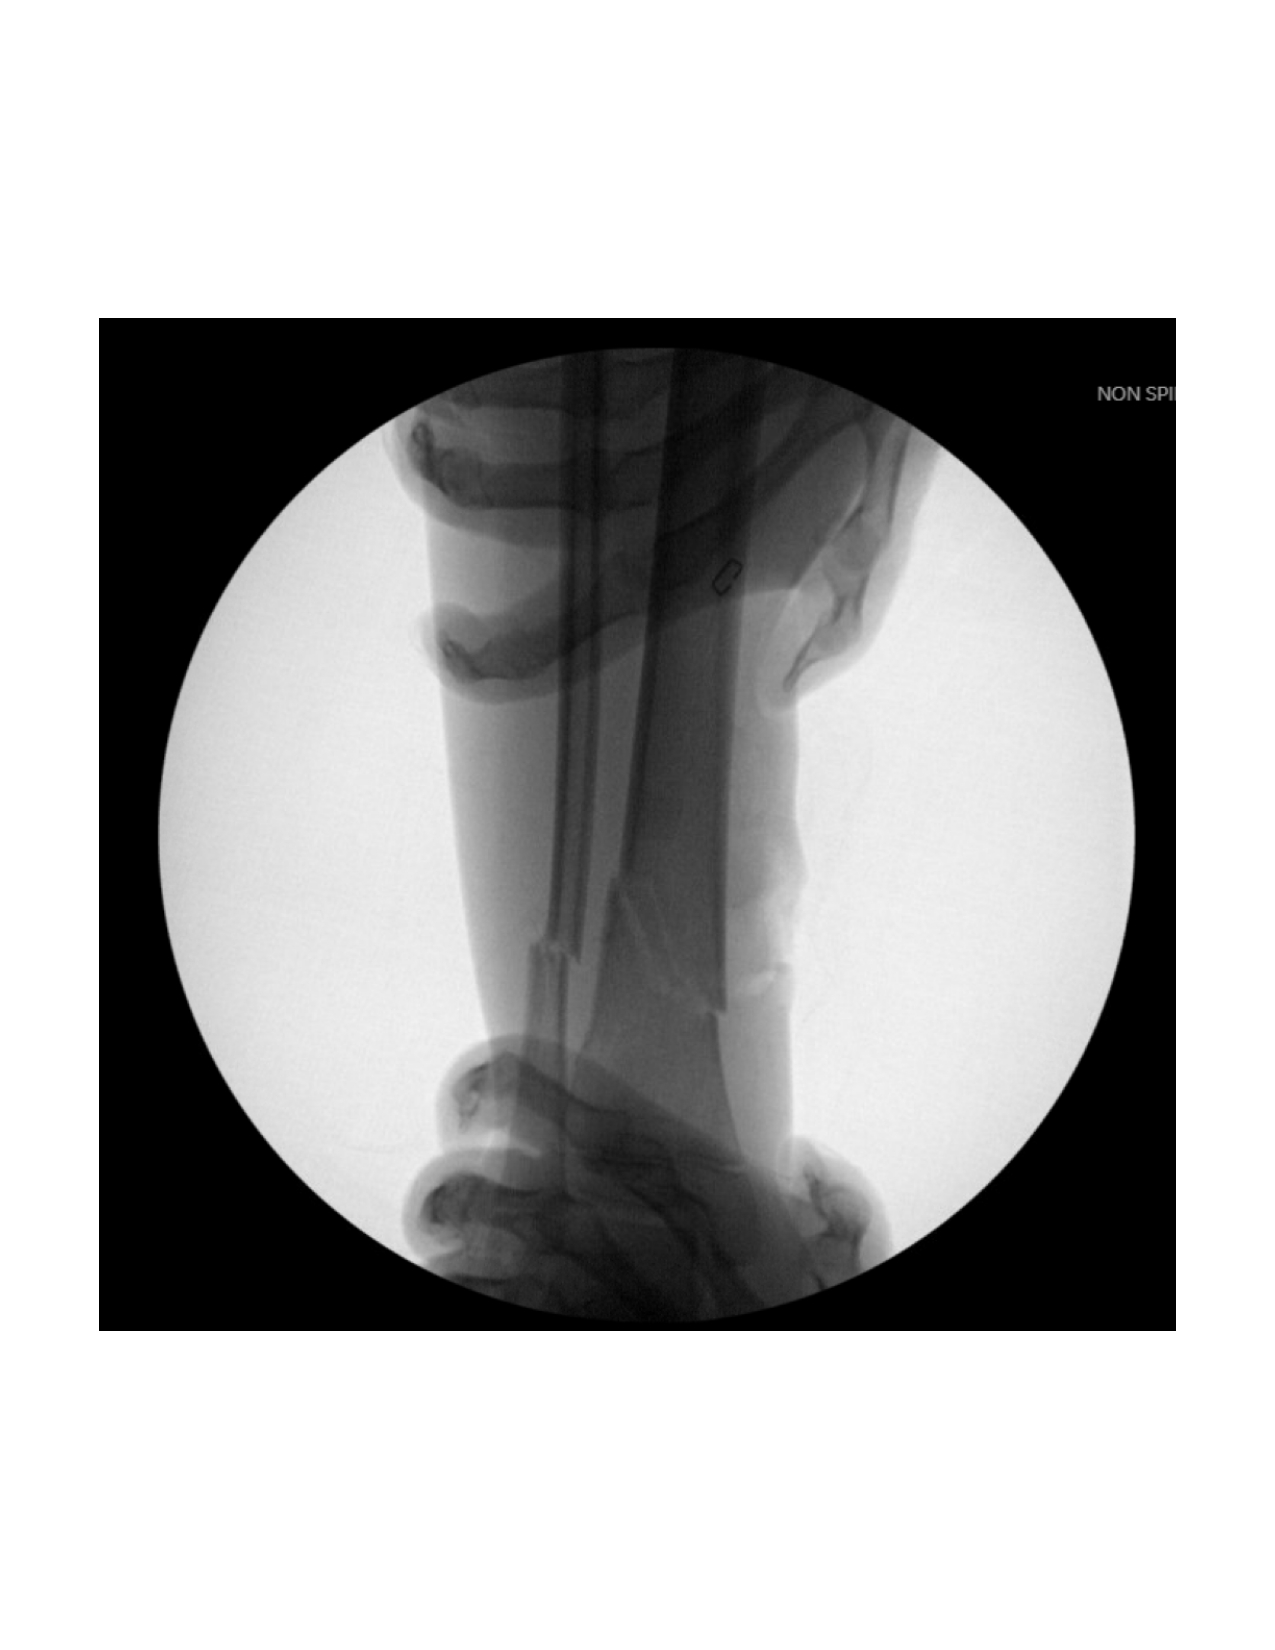

First, fluoroscopy is utilized to identify the fracture site. The mobility of the distal fragment is assessed and a provisional reduction is attempted (Figure 2).

Next, the fracture is manually reduced and both nails are gently advanced past the fracture site by mallet. The curvature of the nails and their tips assists in reducing and stabilizing the fracture, inserted shy of the growth plate. Nail positioning is confirmed by fluoroscopy (Figure 5).

The fracture site is then reassessed under fluoroscopy to confirm maintained reduction. (Figure 8 and Figure 9) Wounds are irrigated and closed in two layers, followed by sterile dressing and short leg splint application.